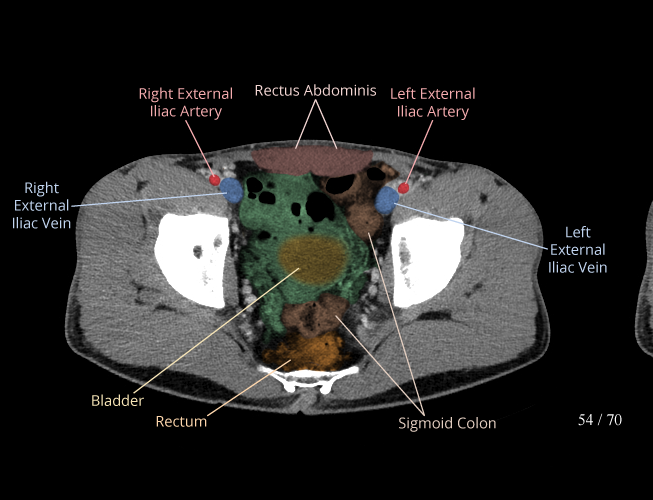

Body

Covers abdominal CT anatomy.